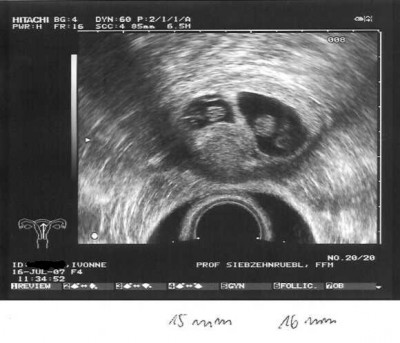

Ab heute ist es Amtlich wir bekommen Zwillinge

beide Herzlein schlagen. Wir können unser Glück garnicht fassen.

Den US hat heute Fr. Dr. Weidner gemacht, da in der Praxis wohl jemand Kollabiert ist und sie Daher unter Zeitdruck gestanden haben. Beide Babys waren gut zu sehen das eine ist 15mm und das andere 16mm groß. Allerdings hat Fr.Dr Weidner gesagt das ich von der Entwicklung her erst in der 7+6 wäre.

Schon schön anzusehen dein US Bild, SCCCHHHÖÖNNNN.